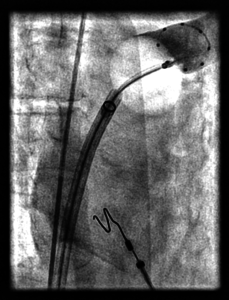

Die Durchführung entspricht der elektrophysiologischen Untersuchung. Am Vortag werden beide Leistenregionen rasiert, um Infektionen vorzubeugen. Am Untersuchungstag muss der Patient nüchtern sein. Zu Beginn der Untersuchung wird der Patient mit einem EKG und zwei Elektroden zur Unterbrechung von möglichen Rhythmusstörungen aus der Herzkammer, den Defibrillatorelektroden, versehen. Nach einer örtlichen Betäubung der Leistenbeuge bringt der Arzt in die Venen des Beines eine Schleuse ein, eine aus Kunststoff bestehende Hülse, über die mehrere spezielle Katheter eingeführt und unter Röntgenkontrolle an verschiedene Stellen des Herzens platziert werden.

Wenn zudem elektrische Signale aus der linken Herzhälfte abgeleitet werden müssen, wird zusätzlich ein Katheter über die Schlagader des Beines (Leistenarterie) eingeführt.

Implantation

Die Implantation des sog. LAA Okkluders führen wir im Herzkatheterlabor unter leichter Narkose und Kontrolle mittels transösophagealer Echokardiographie (Schluckecho) durch. Über einen Katheter, der über die große Vene in der Leiste zum Herzen vorgebracht wird und unter Röntgendarstellung die Vorhofscheidewand passiert (sog. Transseptale Punktion), platzieren wir das passende Verschlusssystem im linken Vorhofohr unter Röntgen- und Ultraschallkontrolle. Mittels Widerhäckchen krallt es sich in das Muskelgewebe des Vorhofohres und wächst über Wochen vollständig ein. Der Eingriff dauert ca. eine Stunde.